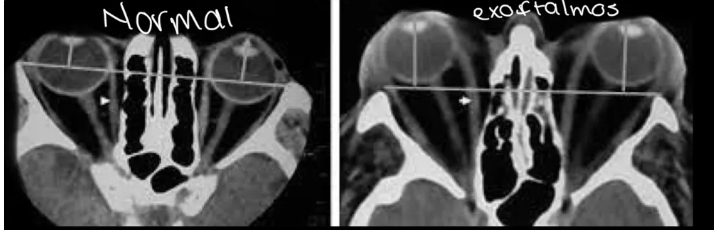

qué esperas ver en una TC por exoftalmos

protrusión ocular anormal, Disociación índice globo ocular-línea intercigomática (Si línea no cruza los ojos es anormal)

Qué esperas ver en una RM de exoftalmos

Protusion ocular anormal, Disociación índice ocular-línea intercantal y Masas ocupativas retroocular